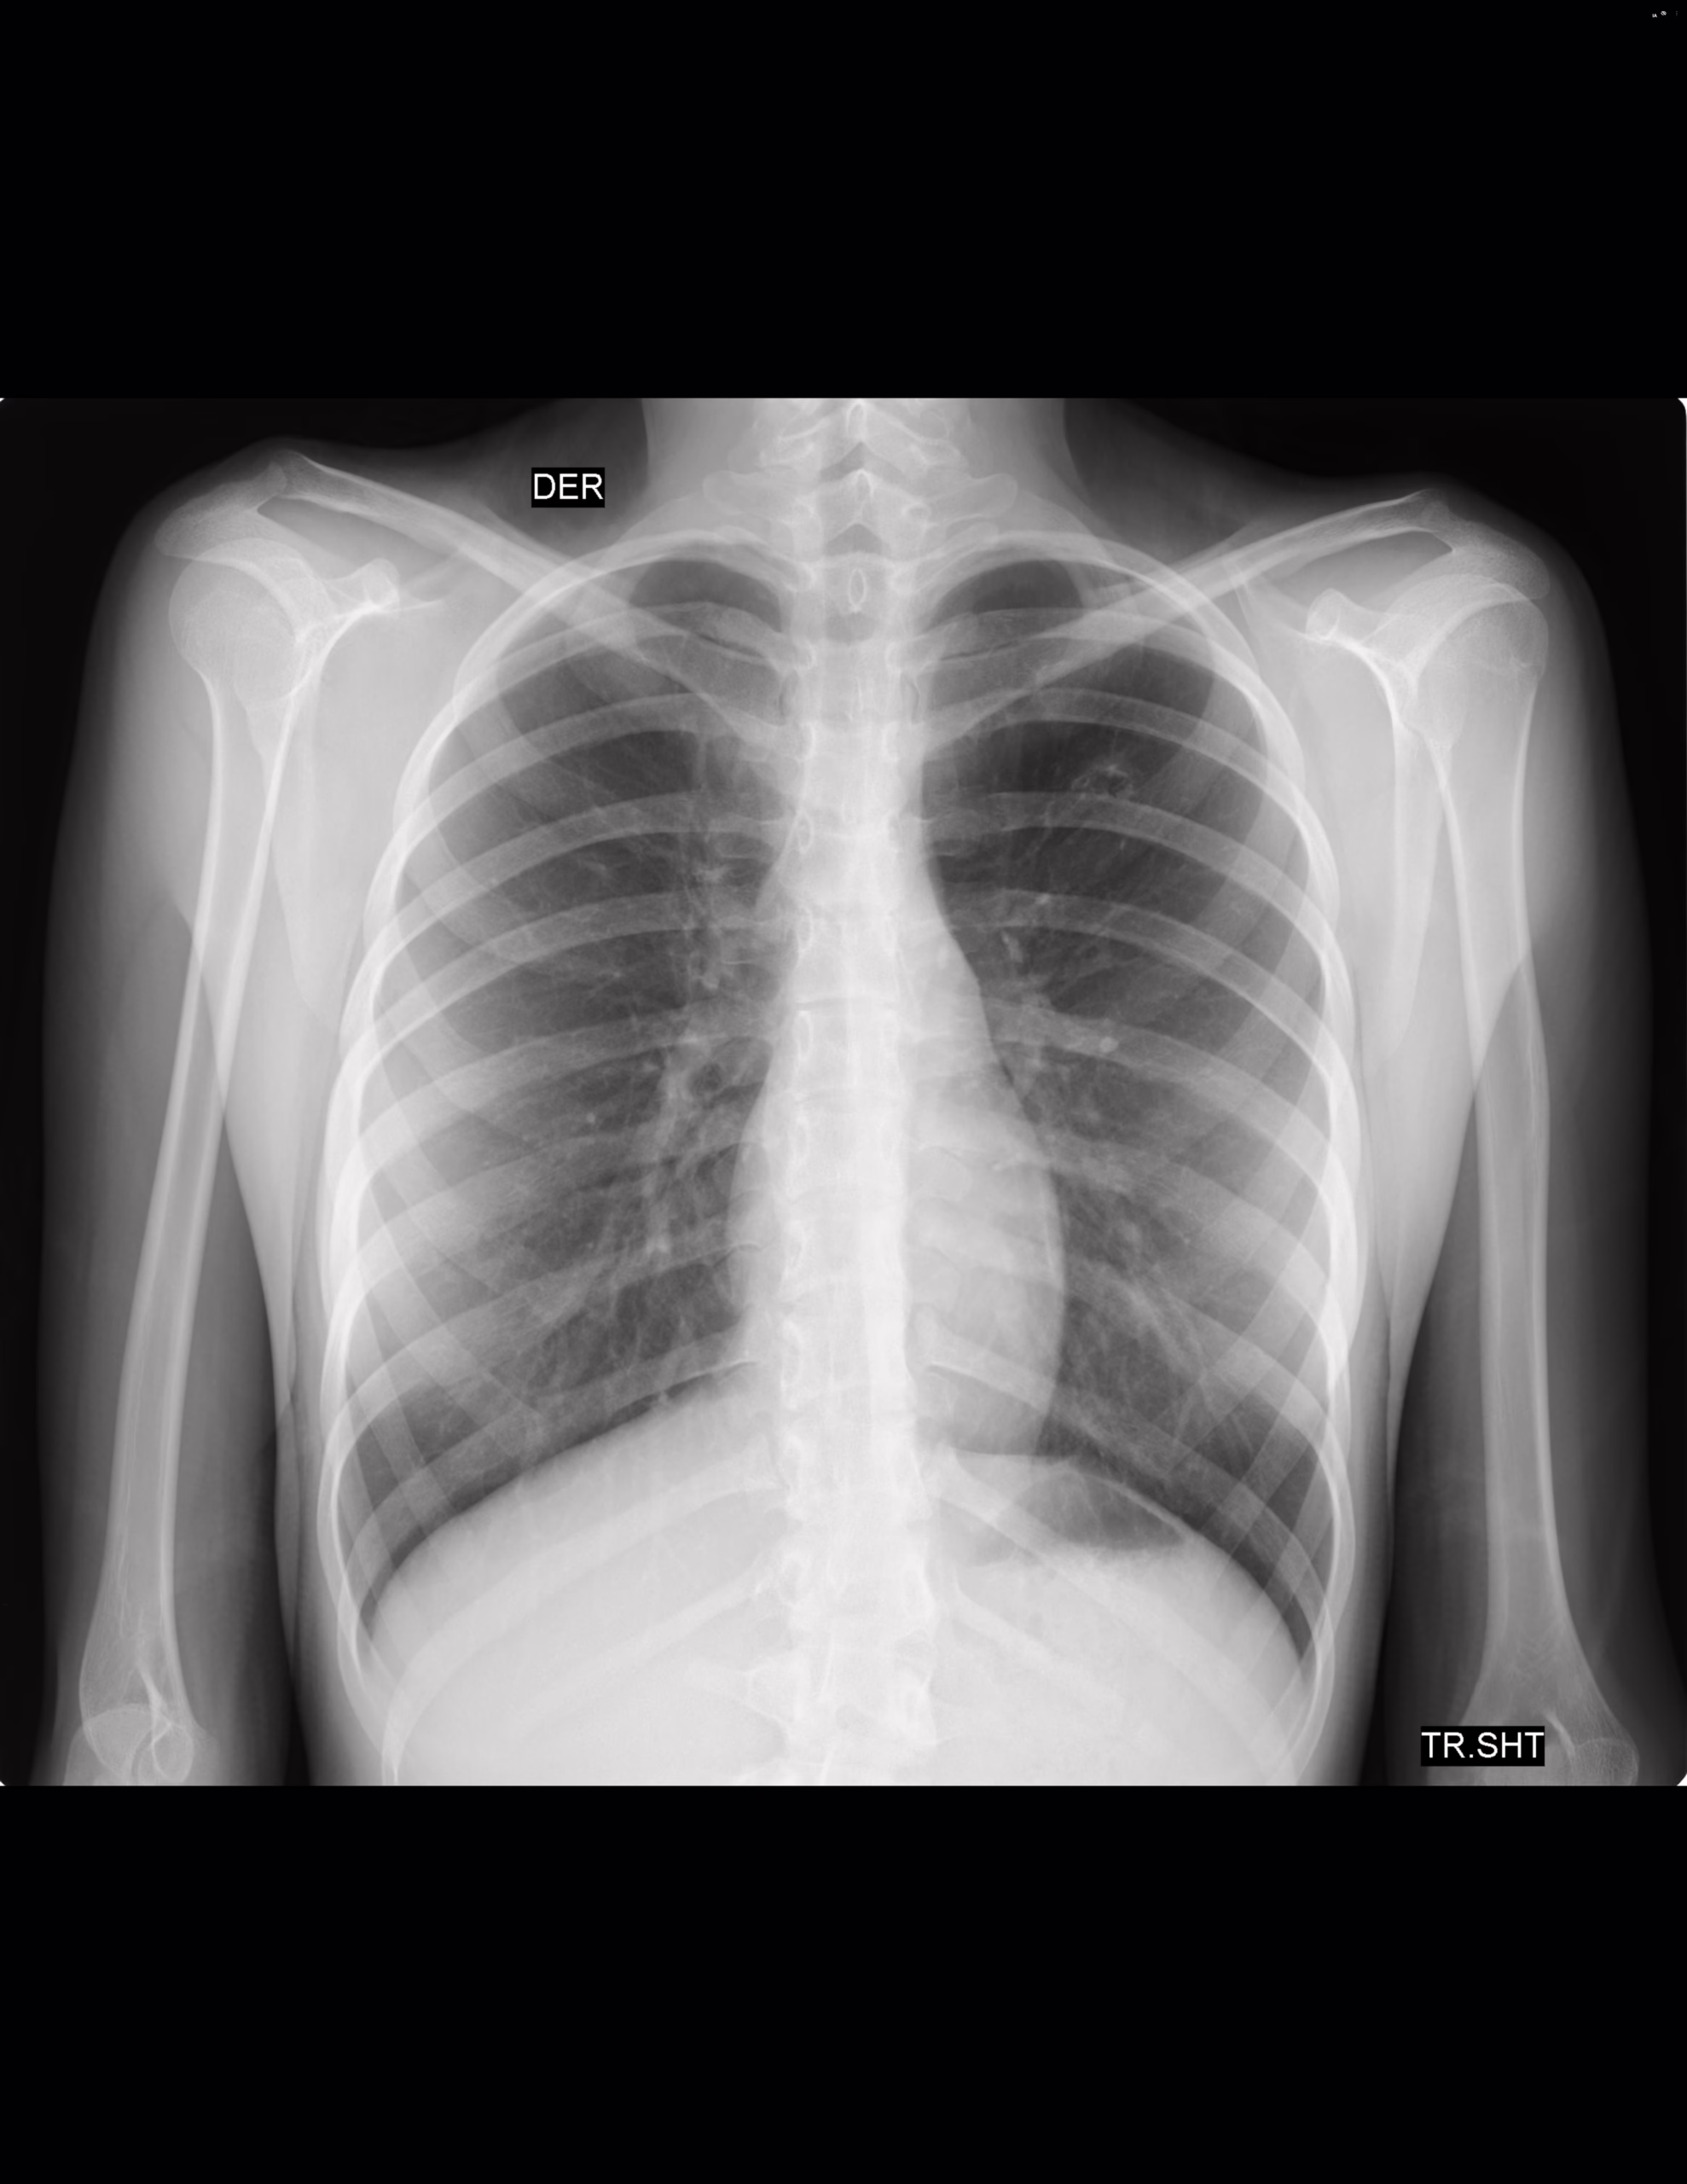

PA Y LATERAL DE TORAX

LA PROYECCION RADIOLOGICA OBTENIDA NOS MUESTRA LOS SIGUIENTES HALLAZGOS:

-Tejidos blandos, con adecuada densidad, sin evidencia alteraciones.

-Estructuras óseas, sin evidencia de lesiones líticas, blásticas o perdida de la contigüidad. Existe rectificación de cifosis dorsal.

-Vía aérea permeable, tráquea central. Botón aórtico sin calcificaciones.

-Mediastino, conservando sus diámetros.

-Corazón, central, con índice cardiotorácico menor a 0.5

-Hilios pulmonares, sin evidencia de alteraciones.

-Trama bronco-vascular, con adecuado trayecto densidad.

-Campos pulmonares, izquierdo hacia lóbulo superior, con presencia de cavitación que mide 5.4 X 10.5 mm, paredes con grosor de hasta 2.13 mm. Resto con adecuada densidad, sin evidencia de opacificaciones, nódulos, masas o derrame pleural.

-Recesos cardiofrénicos y costofrénicos, se observan libres.

-Espacio retroesternal, con adecuada amplitud, sin alteraciones.

OPINIÓN RADIOLÓGICA:

EN EL PRESENTE ESTUDIO RADIOGRÁFICO, CAMPO PULMONAR IZQUIERDO, HACIA LÓBULO SUPERIOR, CON PRESENCIA DE CAVITACIÓN DE ORIGEN A DETERMINAR.

RECTIFICACIÓN DE CIFOSIS DORSAL.